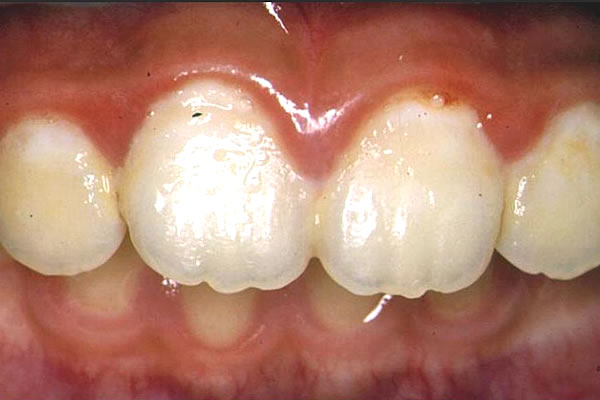

次の写真は、患児が1週間前に初診で来たときのものである。

(図2)

小学校2年生の前歯(初診時)

これを見て驚かされる。

1週間前は、もっと多量の歯垢が付いていたではないか・・・。

歯肉炎や白濁があるとはいえ、1週間前より良い状態である。

冒頭の写真の状態で、「もう少していねいに・・・」と言ってしまえば、患児の努力は泡となる。

これでは良好な信頼関係は得られない。